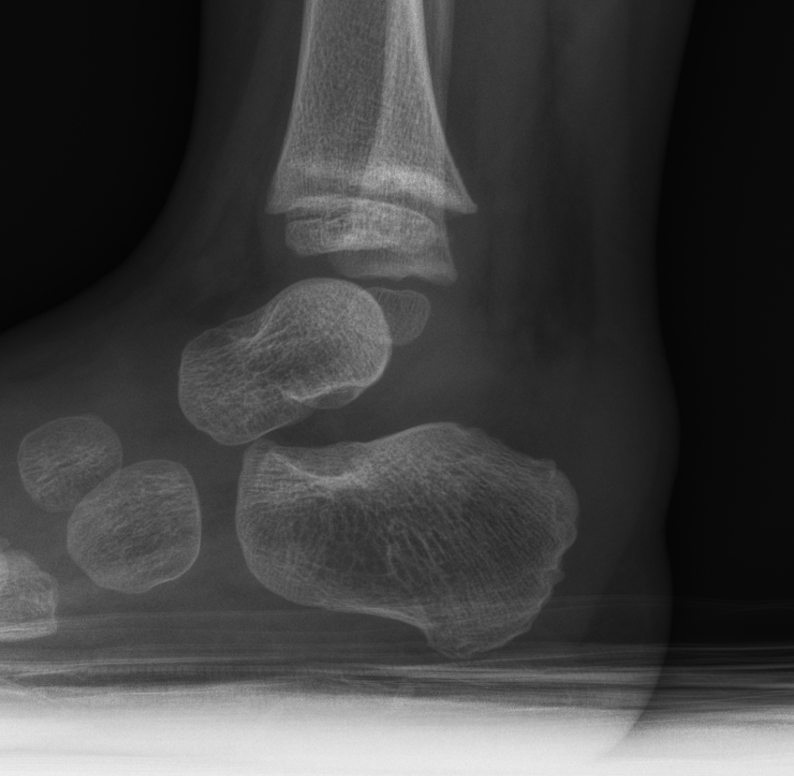

Quiz- what do you think?

Hello, Enjoy the case and send the plausible diagnosis and what would you do about this lesion? Answer will come later today. For more guidance- register and attend tomorrow at noon CT, June 10th. It says ACL but actually, it’s on OT-RADS www.acoredu.com/webinar/acl-injuries-pre-and-post-op/ Best! AC ________________________________ UT Southwestern Medical Center The future of medicine, today. […]